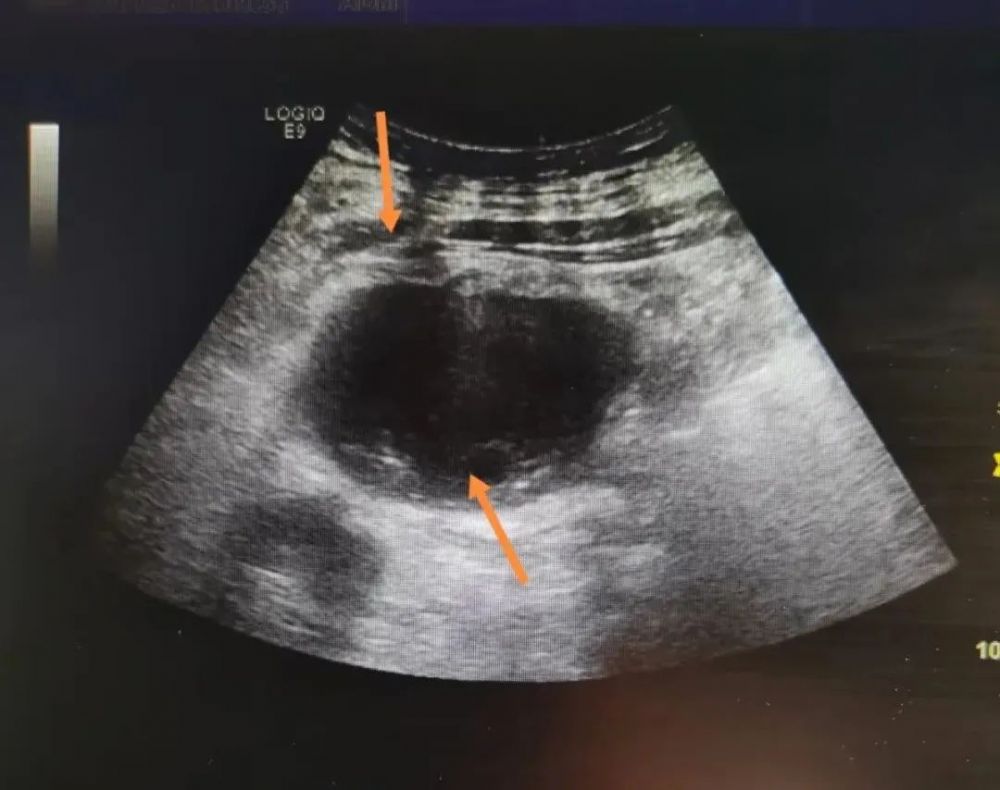

经超声检查发现,患者肝内多发类囊性团块,考虑脓肿。因患者年龄较大,手术耐受程度差,内三组主治医师韩凯与超声科会诊,超声科主任邵宏增、主治医师高珊珊根据患者病情制定详细的治疗方案,因常规手术创伤大,术后恢复困难,最终决定采用超声引导下经皮肝脓肿穿刺置管引流术。

经过积极抗感染及运用超声引导下肝脓肿穿刺引流等综合治疗,患者病情逐渐控制,体温恢复正常,脓肿缩小,病情得到了有效控制。